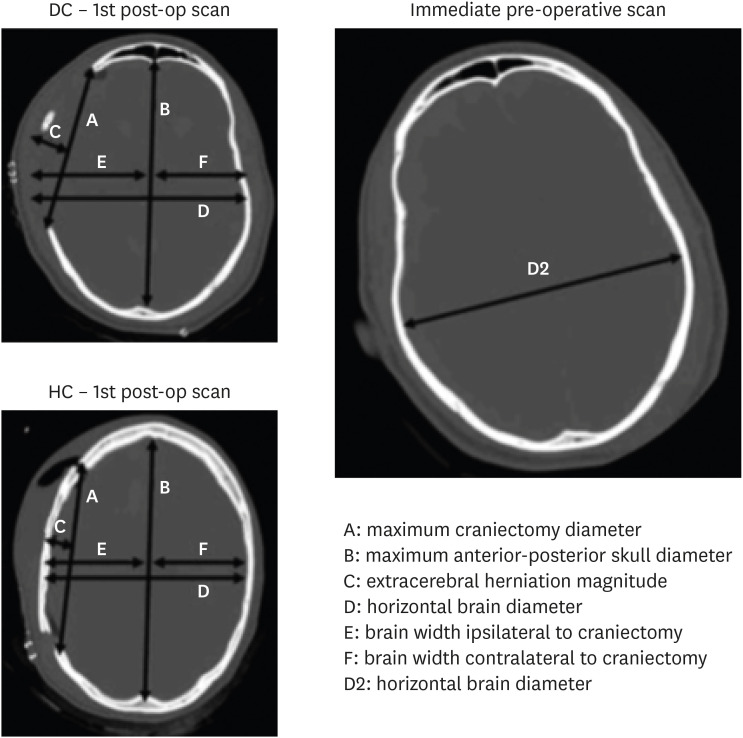

Objective: This randomized controlled trial (RCT) aimed to compare the short-, mid-, and long-term outcomes in patients with malignant intracranial hypertension undergoing either decompressive craniectomy (DC) or hinge craniotomy (HC).

Methods: In this prospective RCT, 38 patients diagnosed with malignant intracranial hypertension due to ischemic infarction, traumatic brain injury, or non-lesional spontaneous intracerebral hemorrhage, who required cranial decompression, were randomly allocated to the DC and HC groups.

Results: The need for reoperation, particularly cranioplasty, in the DC group was significantly different from that in the HC group. The percentage of brain expansion was higher in the DC group versus the HC group; however, the difference was not significant. There was no significant intergroup difference in the functional outcome according to the modified Rankin Scale or the Glasgow Outcome Scale. Additionally, no significant intergroup differences were observed in the rates of in-hospital complications.

Conclusion: The HC and DC groups did not significantly differ in the rate of hospital complications such as infection, need for reoperation owing to the lack of intracranial pressure control, wound healing problems, or bone infection. Our results suggest that by performing HC, the probability of the need for major surgery (cranioplasty) is reduced, thereby removing financial burden from the patient and the health system.